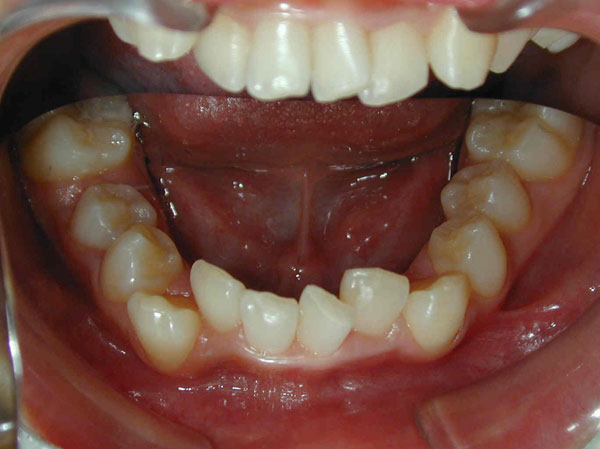

下の前歯が上の前歯より前に出ている噛み合わせが逆になっている状態を下顎前突(受け口)と言います。

横顔がしゃくれたような感じになっていることが多いです。

矯正治療だけで治る場合もありますが、外科手術が必要になることもあります。